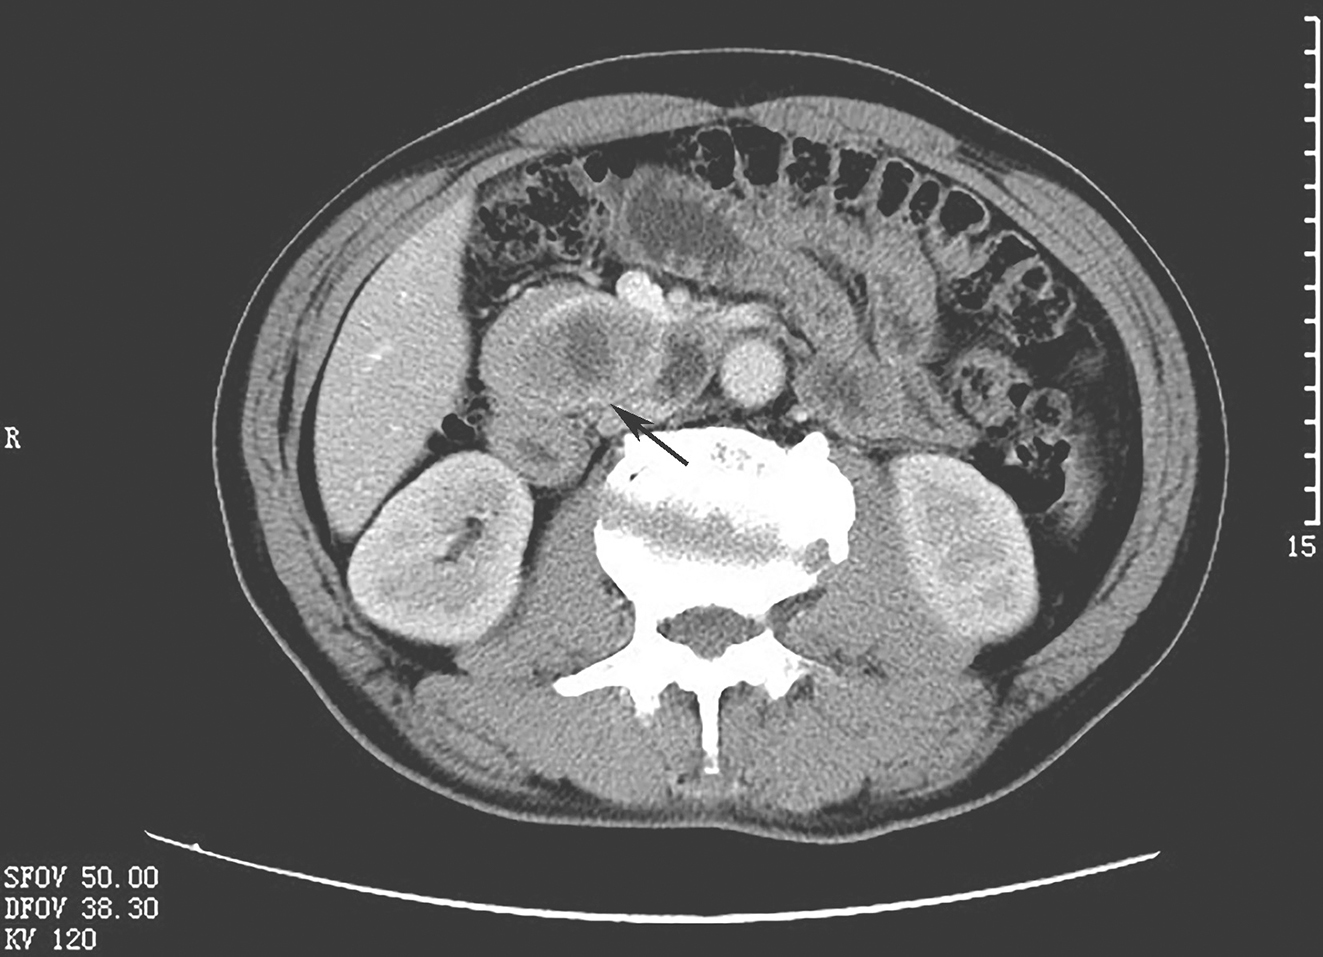

上腹部增强CT(图1):胰腺钩突部软组织肿块,约4.2cm×4.6cm,内见低密度无强化区,余实性部分欠均匀明显强化,压迫十二指肠水平段。肝右叶钙化结节,约1.3cm×0.8cm,另肝脏多发小囊性病灶。胆管未见扩张,胆囊不大,壁不厚,内未见明显异常密度。脾大小正常,密度均匀。双肾囊性病灶,肾上腺未见异常。后腹膜主动脉旁未见肿大淋巴结。影像诊断:①胰腺钩突部肿块,恶性首先考虑;②肝右叶钙化结节,肝脏、双肾多发小囊肿。

图1腹部CT扫描提示十二指肠降部和胰腺钩突部之间肿物